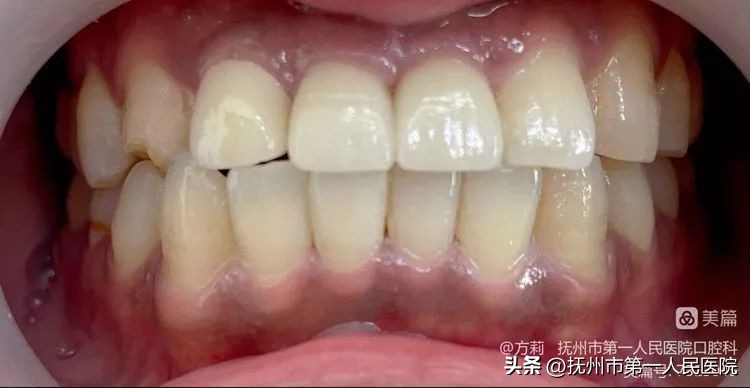

第五步:永久修复体试戴完成

2023年4月,12、11、21永久修复体试戴完成!图为患者口内唇侧观!

患者口内侧面观!

患者口内腭侧照!植体实现了腭侧穿出位,形成良好的穿龈轮廓,且减少了侧向力,利于种植体的长期稳定性!

患者口内切缘观显示:11、21根面突度恢复良好,一定程度上实现了轮廓美学!